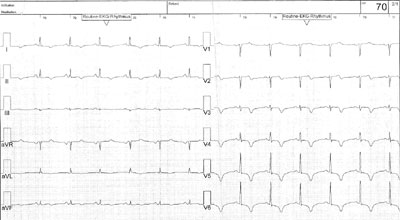

EKG Quiz 52

Eine 61-jährige, gesunde Patientin erleidet einen Skiunfall mit kurzer Bewusstlosigkeit. Ein Schädel CT ergibt keine Hinweise für intrakranielle Pathologien.

Vorgängig wurden weder eine Angina pectoris noch Palpitationen beklagt. Bei Spitaleintritt zeigt sich nebst erhöhten kardialen Biomarkern folgendes EKG:

Ruhe EKG

Wie interpretieren Sie das EKG?